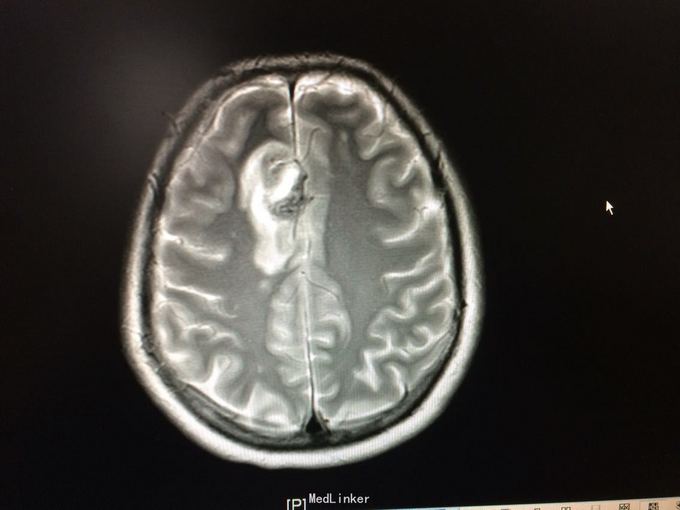

主诉:记忆力减退3月,左侧肢体乏力3天 病史:患者51岁女性,3月前无明显诱因出现记忆力减退,伴头痛,3天前出现站立不稳,左侧肢体乏力,步行困难,当地CT提示右侧额叶低密度灶,

查体:左侧上肢肌力4级,右侧5级,轻瘫试验左侧阳性 辅助检查:右侧额叶、胼胝体膝部病变伴出血,增强扫描明显强化。考虑胶质瘤

诊断:右侧额叶多发脑软化灶 处理:全麻下行右侧额叶占位病变切除术,术后病理提示:符合脑软化,未见明显肿瘤因素等